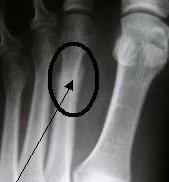

Avulsion Fractures

- Part of bone separated by forceful sudden resisted muscle action

- Caused by ligament or tendon pull on bone

- Part of bone avulsed – bone weaker than tendon/ligament